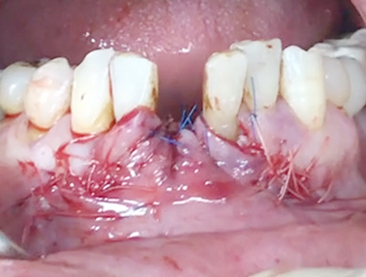

Implants/Bone Grafting

Simultaneous bone graft and implant placement